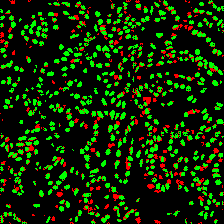

Microscopic image segmentation is a challenging task, wherein the objective is to assign semantic labels to each pixel in a given microscopic image. While convolutional neural networks (CNNs) form the foundation of many existing frameworks, they often struggle to explicitly capture long-range dependencies. Although transformers were initially devised to address this issue using self-attention, it has been proven that both local and global features are crucial for addressing diverse challenges in microscopic images, including variations in shape, size, appearance, and target region density. In this paper, we introduce SA2-Net, an attention-guided method that leverages multi-scale feature learning to effectively handle diverse structures within microscopic images. Specifically, we propose scale-aware attention (SA2) module designed to capture inherent variations in scales and shapes of microscopic regions, such as cells, for accurate segmentation. This module incorporates local attention at each level of multi-stage features, as well as global attention across multiple resolutions. Furthermore, we address the issue of blurred region boundaries (e.g., cell boundaries) by introducing a novel upsampling strategy called the Adaptive Up-Attention (AuA) module. This module enhances the discriminative ability for improved localization of microscopic regions using an explicit attention mechanism. Extensive experiments on five challenging datasets demonstrate the benefits of our SA2-Net model. Our source code is publicly available at \url{https://github.com/mustansarfiaz/SA2-Net}.